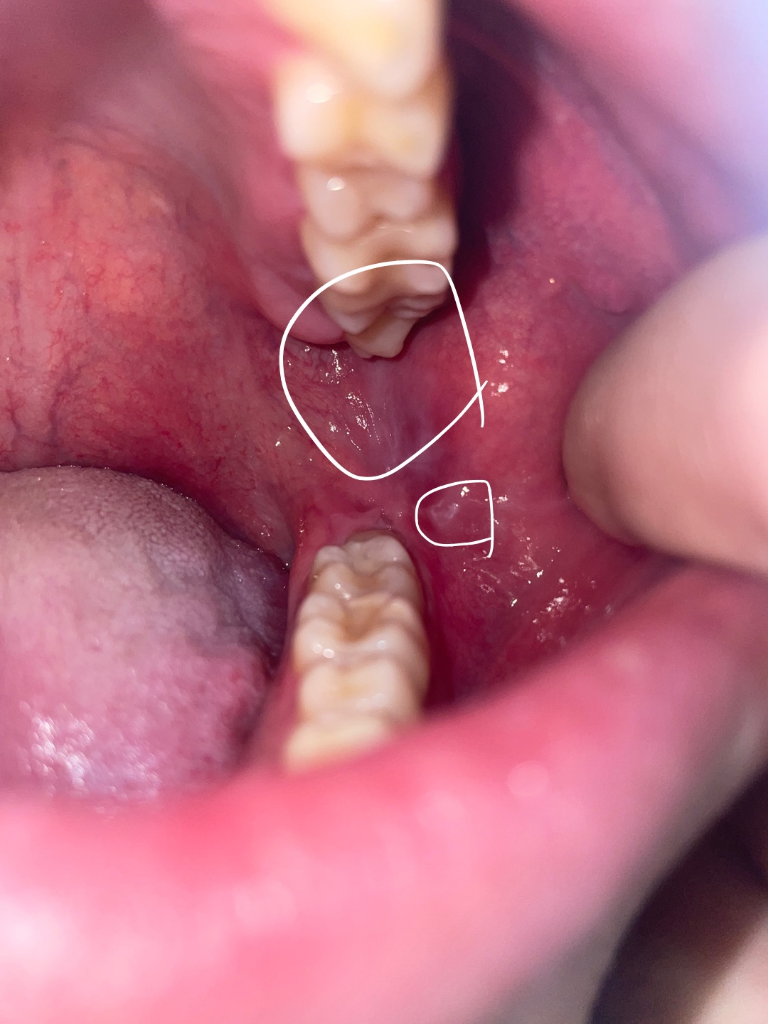

양쪽 어금니 쪽 볼에 혹?처럼 뭐가 생겼어요 깨문기억은 없는데 혹시 구강암이런것과 관련있나요?

한 3일전쯤까진 없었는데 그쯤 양쪽 어금니 쪽에 볼에 혹? 염증? 같은 그런게 생겼어요

그리고 사진에 보면 어금니 뒤쪽 흰색부분이 있는데 이건 왜 그럴까요 이건 언제부터 생긴건지는 모르겠습니다. 잘 안보이실까 하여 표시안한 원본사진도 첨부합니다

해당부위는 볼의 연조직이 치아 사이에 밀려 들어가면서 생기는 증상으로 보입니다.

구강암이 아니고 볼이 치아에 씹혀서 생긴겁니다. 문제가 잇는건 아니니 너무 걱정하지마세요.

사진상으로는 씹어서 생긴 외상성 궤양이 맞습니다

특별히 치아에 보철치료나 충치치료를 하고 생긴 변화가 아니기 때문에 치과적으로 처치를 해줄 건 없고 외상성 궤양도 시간이 지나면 자연스럽게 회복됩니다. 좀 더 빠른 회복을 위해서는 구강 내에 적용하는 연고를 바르셔도 좋습니다.